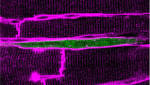

Researchers Reveal Clues Toward Heart Muscle Regeneration

Can we teach heart cells to grow up?